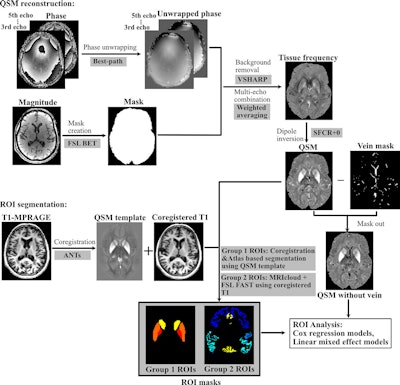

Processing pipeline for quantitative susceptibility mapping (QSM) reconstruction and region-of-interest (ROI) segmentation MRICloud is cloud-based medical image processing software (mricloud.org). ANT = advanced normalization tool, BET = brain extraction tool, FAST = functional MRI of the brain automated segmentation tool, FSL = functional MRI of the brain software library, MPRAGE = magnetization-prepared rapid gradient-echo, SFCR+0 = structural feature–based collaborative reconstruction with auto-referencing to central cerebrospinal fluid, VSHARP = variable radius sophisticated harmonic artifact reduction for phase data.Images and caption courtesy of the RSNA.